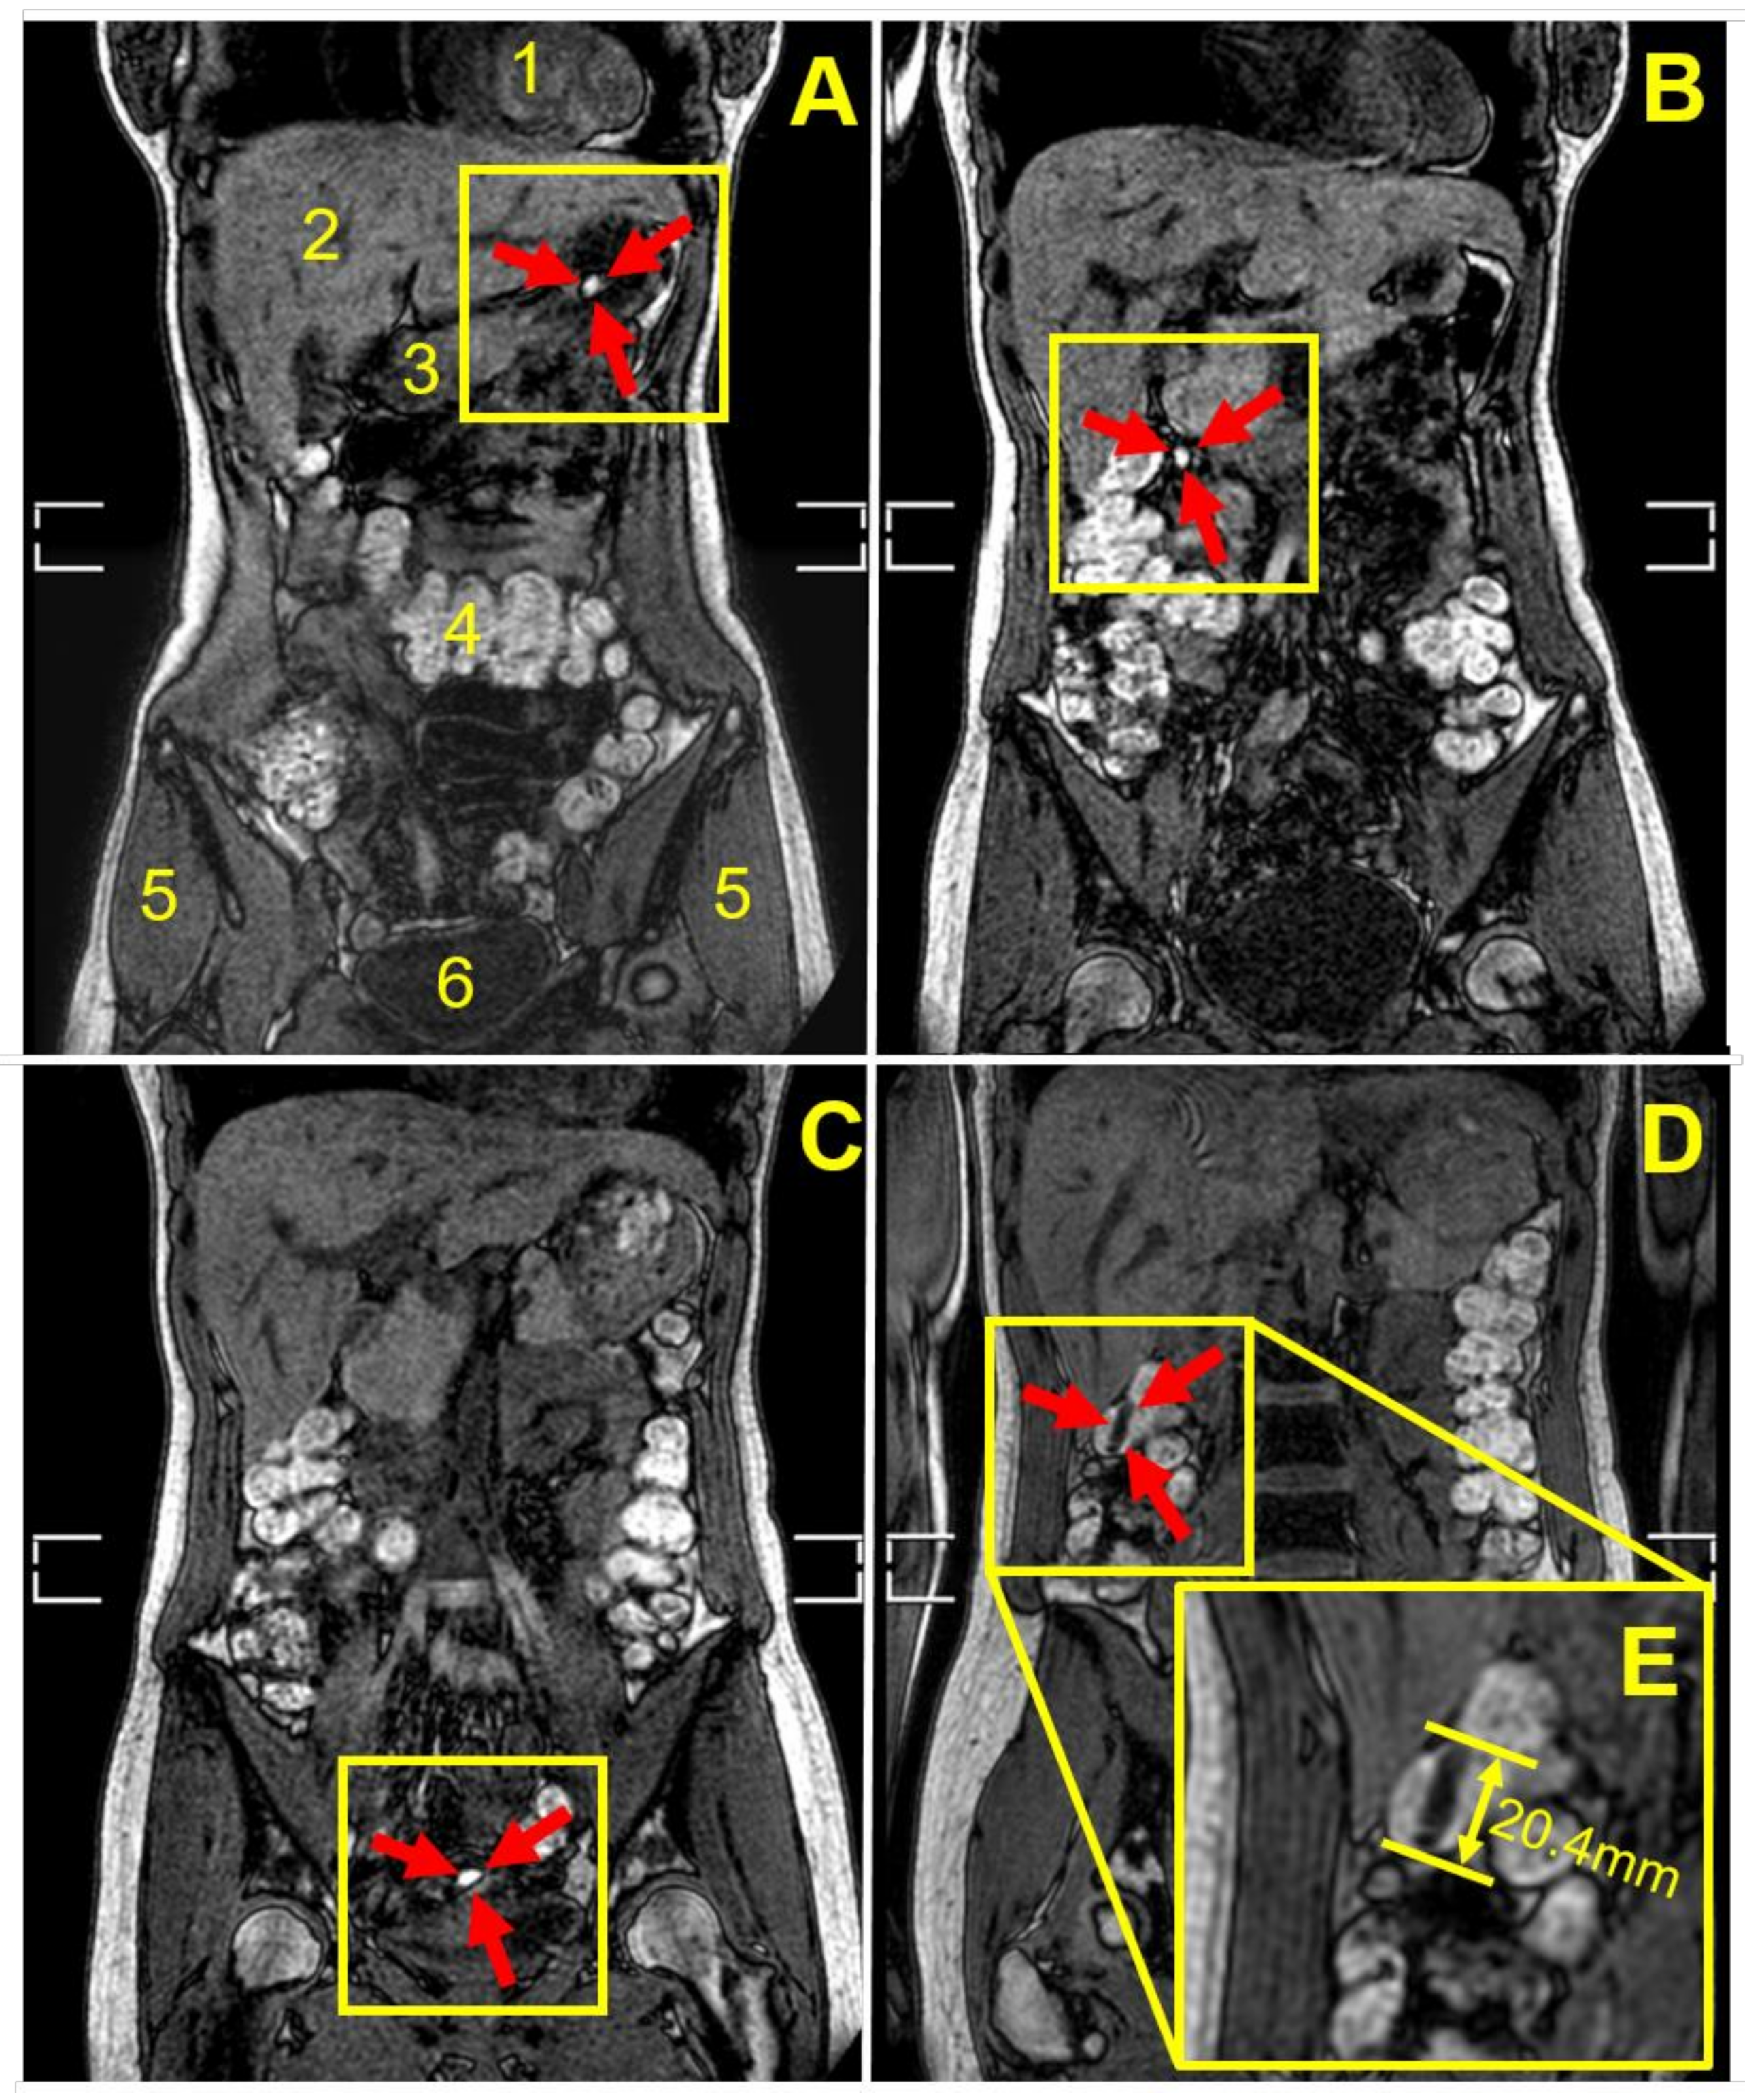

3.3. Capsule Imaging Studies In Vivo

| Participant | Weight Gain (mg) a | Weight Gain Per Surface Area (mg/mm2) | Gastrointestinal Location and Integrity of the Capsule at the Different Imaging Time Points (min) | |||||||

|---|---|---|---|---|---|---|---|---|---|---|

| 45 | 90 | 135 | 180 | 225 | 270 | 315 | 360 | |||

| 1 | 9.2 ± 0.8 | 0.02 | Stomach | Stomach | Stomach b | NO c | NO | NO | NO | NO |

| 2 | 18.2 ± 1.2 | 0.04 | Stomach | Stomach | Duodenum | Duodenum | Term ileum | NO | NO | d |

| 3 | 18.2 ± 1.2 | 0.04 | Stomach | Stomach | Term ileum | Asc colon | Hep flexure | Hep flexure | Hep flexure | Hep flexure |

| 4 | 18.2 ± 1.2 | 0.04 | Stomach | Jejunum | Jejunum | Jejunum | Term ileum | Term ileum | Term ileum | NO |

| 5 | 18.2 ± 1.2 | 0.04 | Stomach | Jejunum | Cecum | Cecum | Asc colon | Asc colon | NO | Hep flexure |

| 6 | 18.2 ± 1.2 | 0.04 | Stomach | Stomach | Term ileum | Term ileum | NO | NO | NO | NO |

| 7 | 18.2 ± 1.2 | 0.04 | Stomach | Jejunum | Jejunum | Term ileum | Term ileum | NO | NO | NO |

| 8 | 36.0 ± 5.2 | 0.08 | Stomach | Jejunum | Term ileum | Cecum | NO | NO | shade | |

| 9 | 52.6 ± 9.7 | 0.11 | Stomach | Duodenum | Term ileum | Hep flexure | Hep flexure | Trans colon | Trans colon | |

| 10 | 52.6 ± 9.7 | 0.11 | Stomach | Stomach | Duodenum | Duodenum | NO | NO | ||